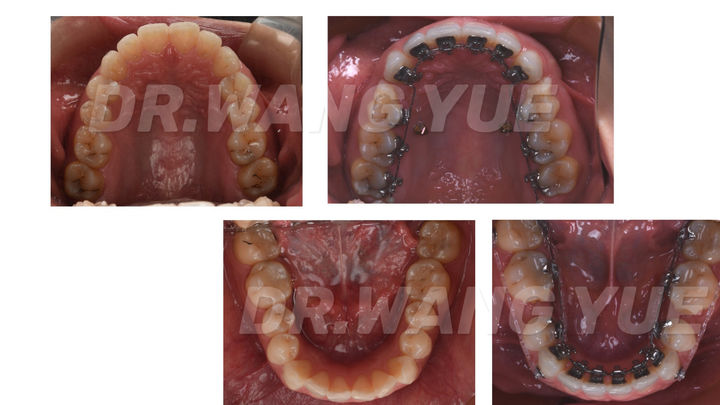

5个月舌侧矫正效果

舌侧内收5个月战报,这是精致ol对侧颜的追求,不变的是整齐,变化的是侧脸的曲线

拔牙后都会给大家做一个小假牙,随着移动间隙越小假牙也随之越小

舌侧矫正是追求速度和美观的最佳选择

阶段性的反馈图值得被记录